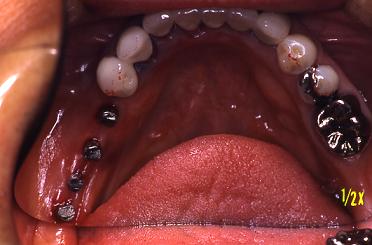

全て鏡に映っています。

冠が入りました